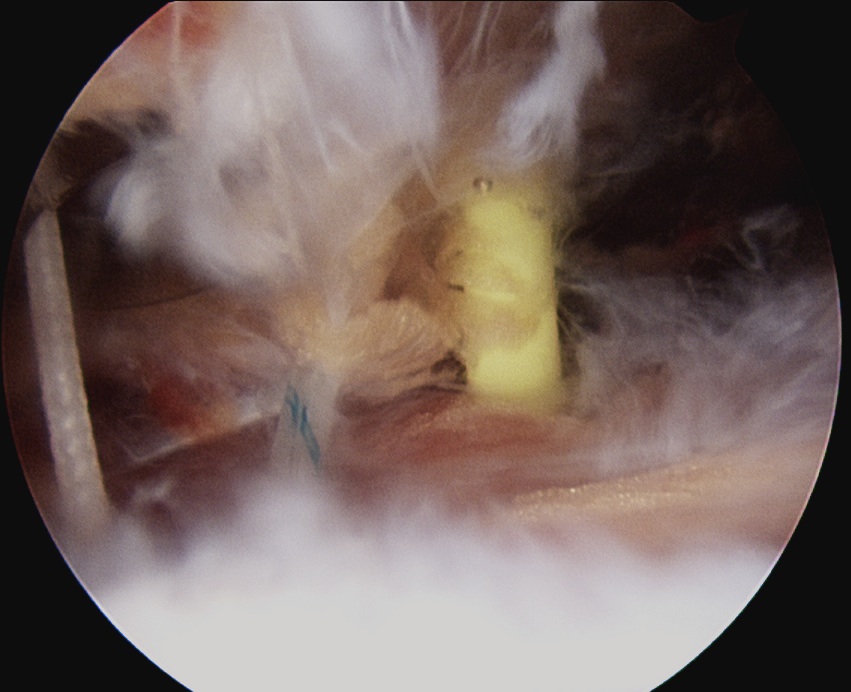

- can tie blind or put camera into subacromial space

Tying knots under direct vision in the subdeltoid space using double pulley technique